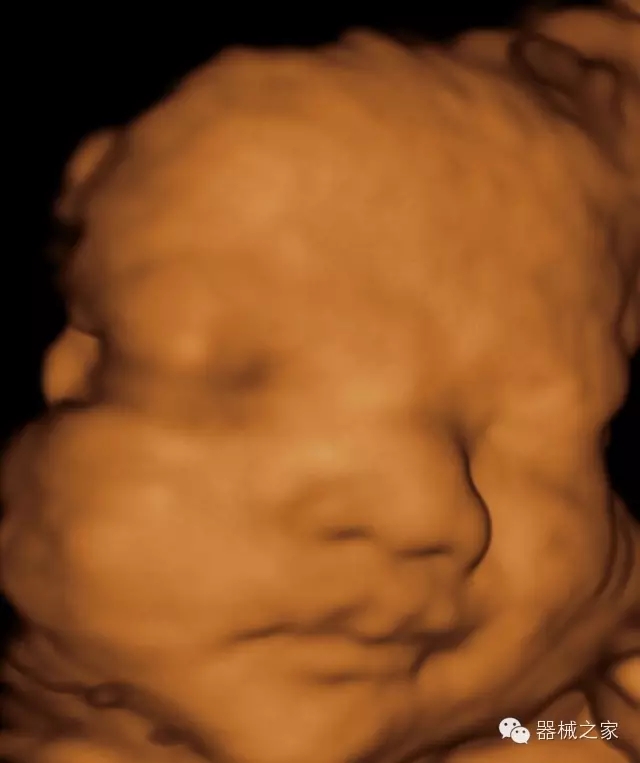

·完整的3D/4D臨床應用,STIC, MCUT 和Auto NT等滿足產(chǎn)科所有應用;

·更高的HQ羊膜腔鏡成像技術精細觀察每一個暗區(qū)細節(jié);

·高效3D/4D成像技術:高速的4D幀頻,豐富的3D成像模式,智能斷層切片功能;